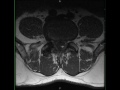

Lumbar Spine Synovial Cyst

62-year-old male with worsening right-sided back pain over a period of two months. There is a well circumscribed T1-hypointense, T2/STIR-hyperintense lesion arising from the facet joint at L4-L5 on the right and extending under the ligamentum flavum. There is mild-moderate bilateral facet arthropathy. The imaging findings are most compatible with a right-sided synovial cyst which contacts the L5 and S1 nerve roots on the right. Spinal synovial cysts are collections of synovial fluid contained by a cuboid or pseudostratified columnar epithelium. The cyst may contain old hemorrhage or proteinaceous debris, which can alter its signal characteristics. Most cases are asymptomatic, but slow growth over time can result in progressive back pain. They tend to occur at the L3-L4 and L4-L5 disc levels.